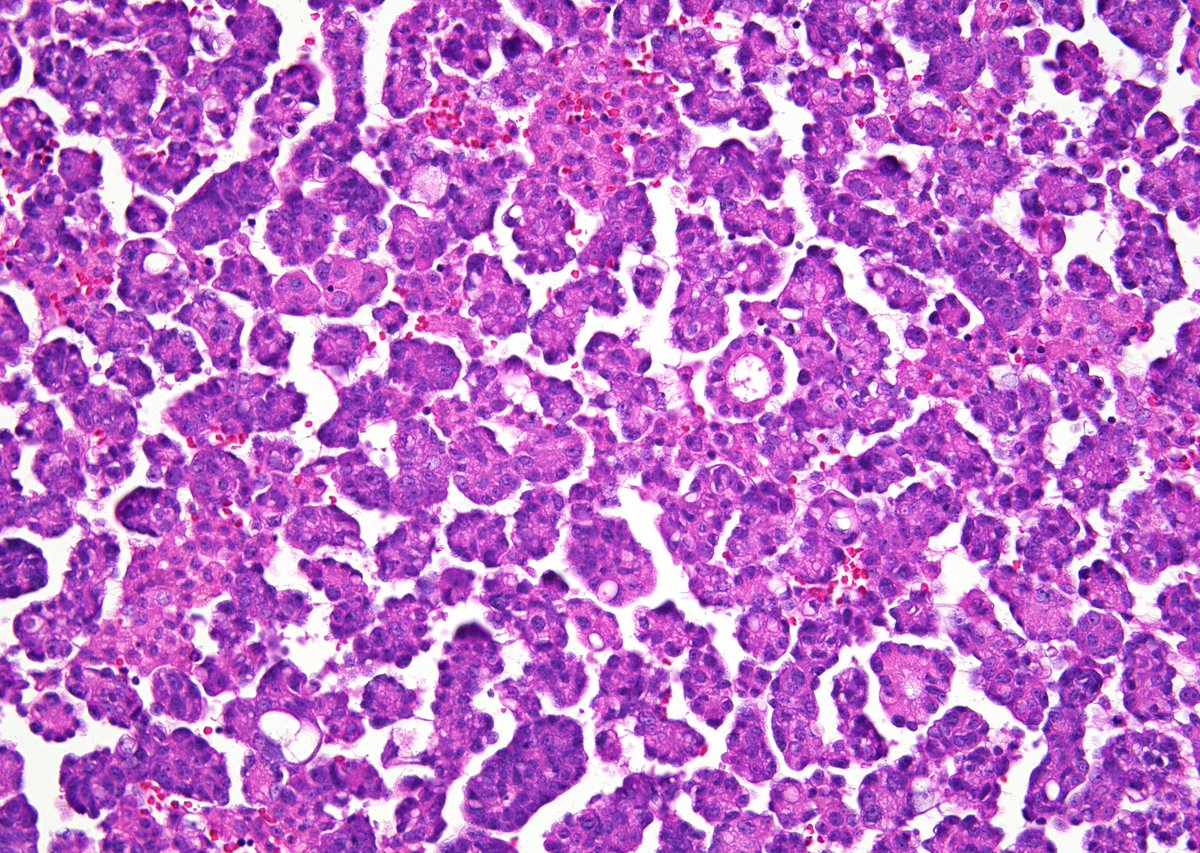

I'm always amazed 😮at how Small CC appears on smears (EBUS-FNA, lung)🫁 🔬Fine/dark chromatin 🔬Absent/inconspicuous nucleoli 🔬Scant/absent cytoplasm 🔬Apoptotic bodies 🔬Paranuclear blue bodies (arrow): dense collections of keratin filaments @IACytology @CytologyEFCS

3

54

124